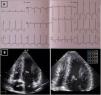

Resting electrocardiogram (ECG) (top) and transthoracic echocardiogram (TTE) (bottom), performed four months after detraining. (A) The ECG shows a clear improvement of the T-wave abnormalities in the inferior and lateral leads, although the ECG is still abnormal; (B) on TTE, a decrease in both septal and apical LV wall thickness is evident (maximum 11 mm). LA: left atrium; LV: left ventricle; RA: right atrium; RV: right ventricle.

Follow-up assessment was performed four months later. He had reportedly respected our warning and barely exercised in the meantime. While still abnormal, the ST-segment depression and deeply inverted T waves had become less prominent (Figure 3). We repeated the TTE and had a similar impression: although maximum wall thickness in the apex was significantly decreased (10-11 mm) and not diagnostic of HCM, the TTE seemed clearly abnormal, given the small cavity, the abnormal geometry and the apical gradient (Figures 3 and 4 and Video 2).

Transthoracic echocardiogram after detraining. Note the abnormal shape of the left ventricular cavity (small cavity size, prominent papillary muscle, with apical cavity obliteration in systole (A) and increased flow velocity (arrow) (B) suggestive of a myopathic left ventricle, rather than adaptive remodeling following training. LA: left atrium; LV: left ventricle; RA: right atrium; RV: right ventricle.